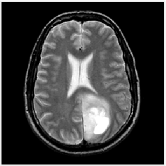

| Query Images |

|

| Segmented Images |